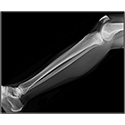

Interactive Radiology